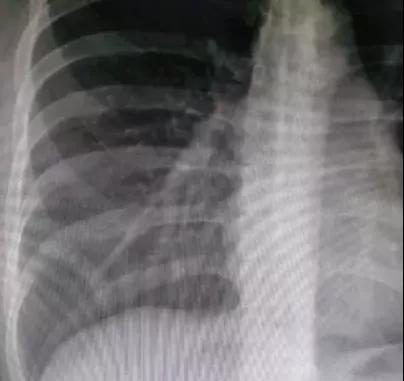

深吸气后屏气拍摄(同比例局部放大)

在观察肺部和腹部微小病变时,若不屏住呼吸,可能产生呼吸伪影,显示不清,影响图像质量,导致诊断不明确,甚至漏诊。